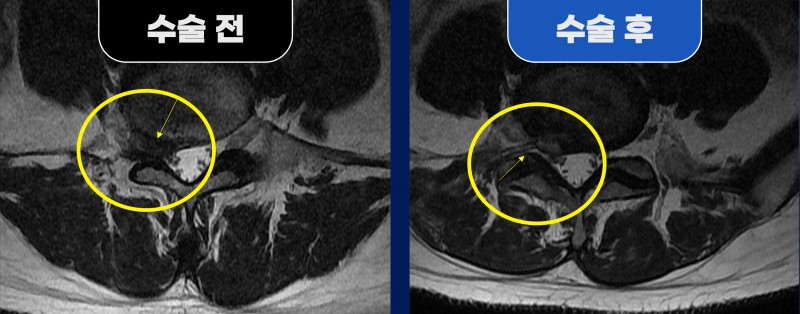

요추 5번/천추 1번 추간판 파열, 단일공 내시경 수술로 해결

■ Before (수술 전)

33세 여성 환자분께서 요추 5번/천추 1번 추간판 파열로 내원하셨습니다.

MRI 결과, 파열된 디스크가 위쪽으로 밀려 올라가면서 추간공을 통해 신경을 심하게 압박하고 있었으며,

다리에 힘이 빠지는 마비 증상까지 동반되었습니다.

신경차단술을 포함한 여러 치료에도 통증이 지속되어 수술이 불가피한 상태였습니다.

특히, 후방으로 접근할 경우 후관절을 많이 제거해야 했고,

반대쪽에서 들어갈 경우 디스크 양이 많아 한 번에 제거하기 어려운 고난도 수술 상황이었습니다.

■ After (수술 후)

이에 따라 우측 추간공을 통한 단일공 내시경 수술을 진행하였고,

파열된 디스크 조각들을 안전하게 제거했습니다.

신경 부종과 압박 부위가 해소되면서 MRI에서도 정상적인 신경 공간이 확보된 것을 확인했습니다.

수술은 국소마취로 진행되었으며, 피부 절개 약 0.8cm, 수술 시간은 약 30~40분이 소요되었습니다.

환자분은 수술 직후부터 통증이 현저히 줄었고, 빠르게 보행이 가능해졌습니다.